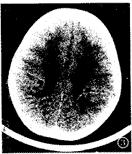

本组病例初次头颅CT扫描时间:最早在生后1天,最迟23天,平均3.8天,诊断为不同程度的 HIE。结合文献[1],根据CT所见的脑水肿范围、程度,将本组HIE分为轻、中、重 3度:轻度者43例,脑实质内斑片状低密度灶,常见于额叶、枕顶叶,合并蛛网膜下腔出血( SAH) 38例,脑室内出血(IVH) 7例,硬膜下血肿(SDH) 1例,脑实质内出血(ICH) 2例,脑室 、脑池大小、形态正常;中度者14例,脑实质内广泛斑片状低密度灶,累及额颞枕顶叶,灰 白质界限模糊,脑室、脑池变窄,合并SAH 7例,IVH 3例,室管膜下出血(SEH)2例;重度 者5例,脑实质内弥漫性低密度灶,灰白质界限消失,脑室、脑池、脑沟变窄或消失(图1), 合并SAH 5例,IVH 1例,SDH 1例,ICH 1例。

图1 重 度HIE:大脑密度普遍性减低,灰白质界限消失,基底节区密度相对较高,右额叶、左枕叶 出血灶,脑室、脑池及脑沟变窄。